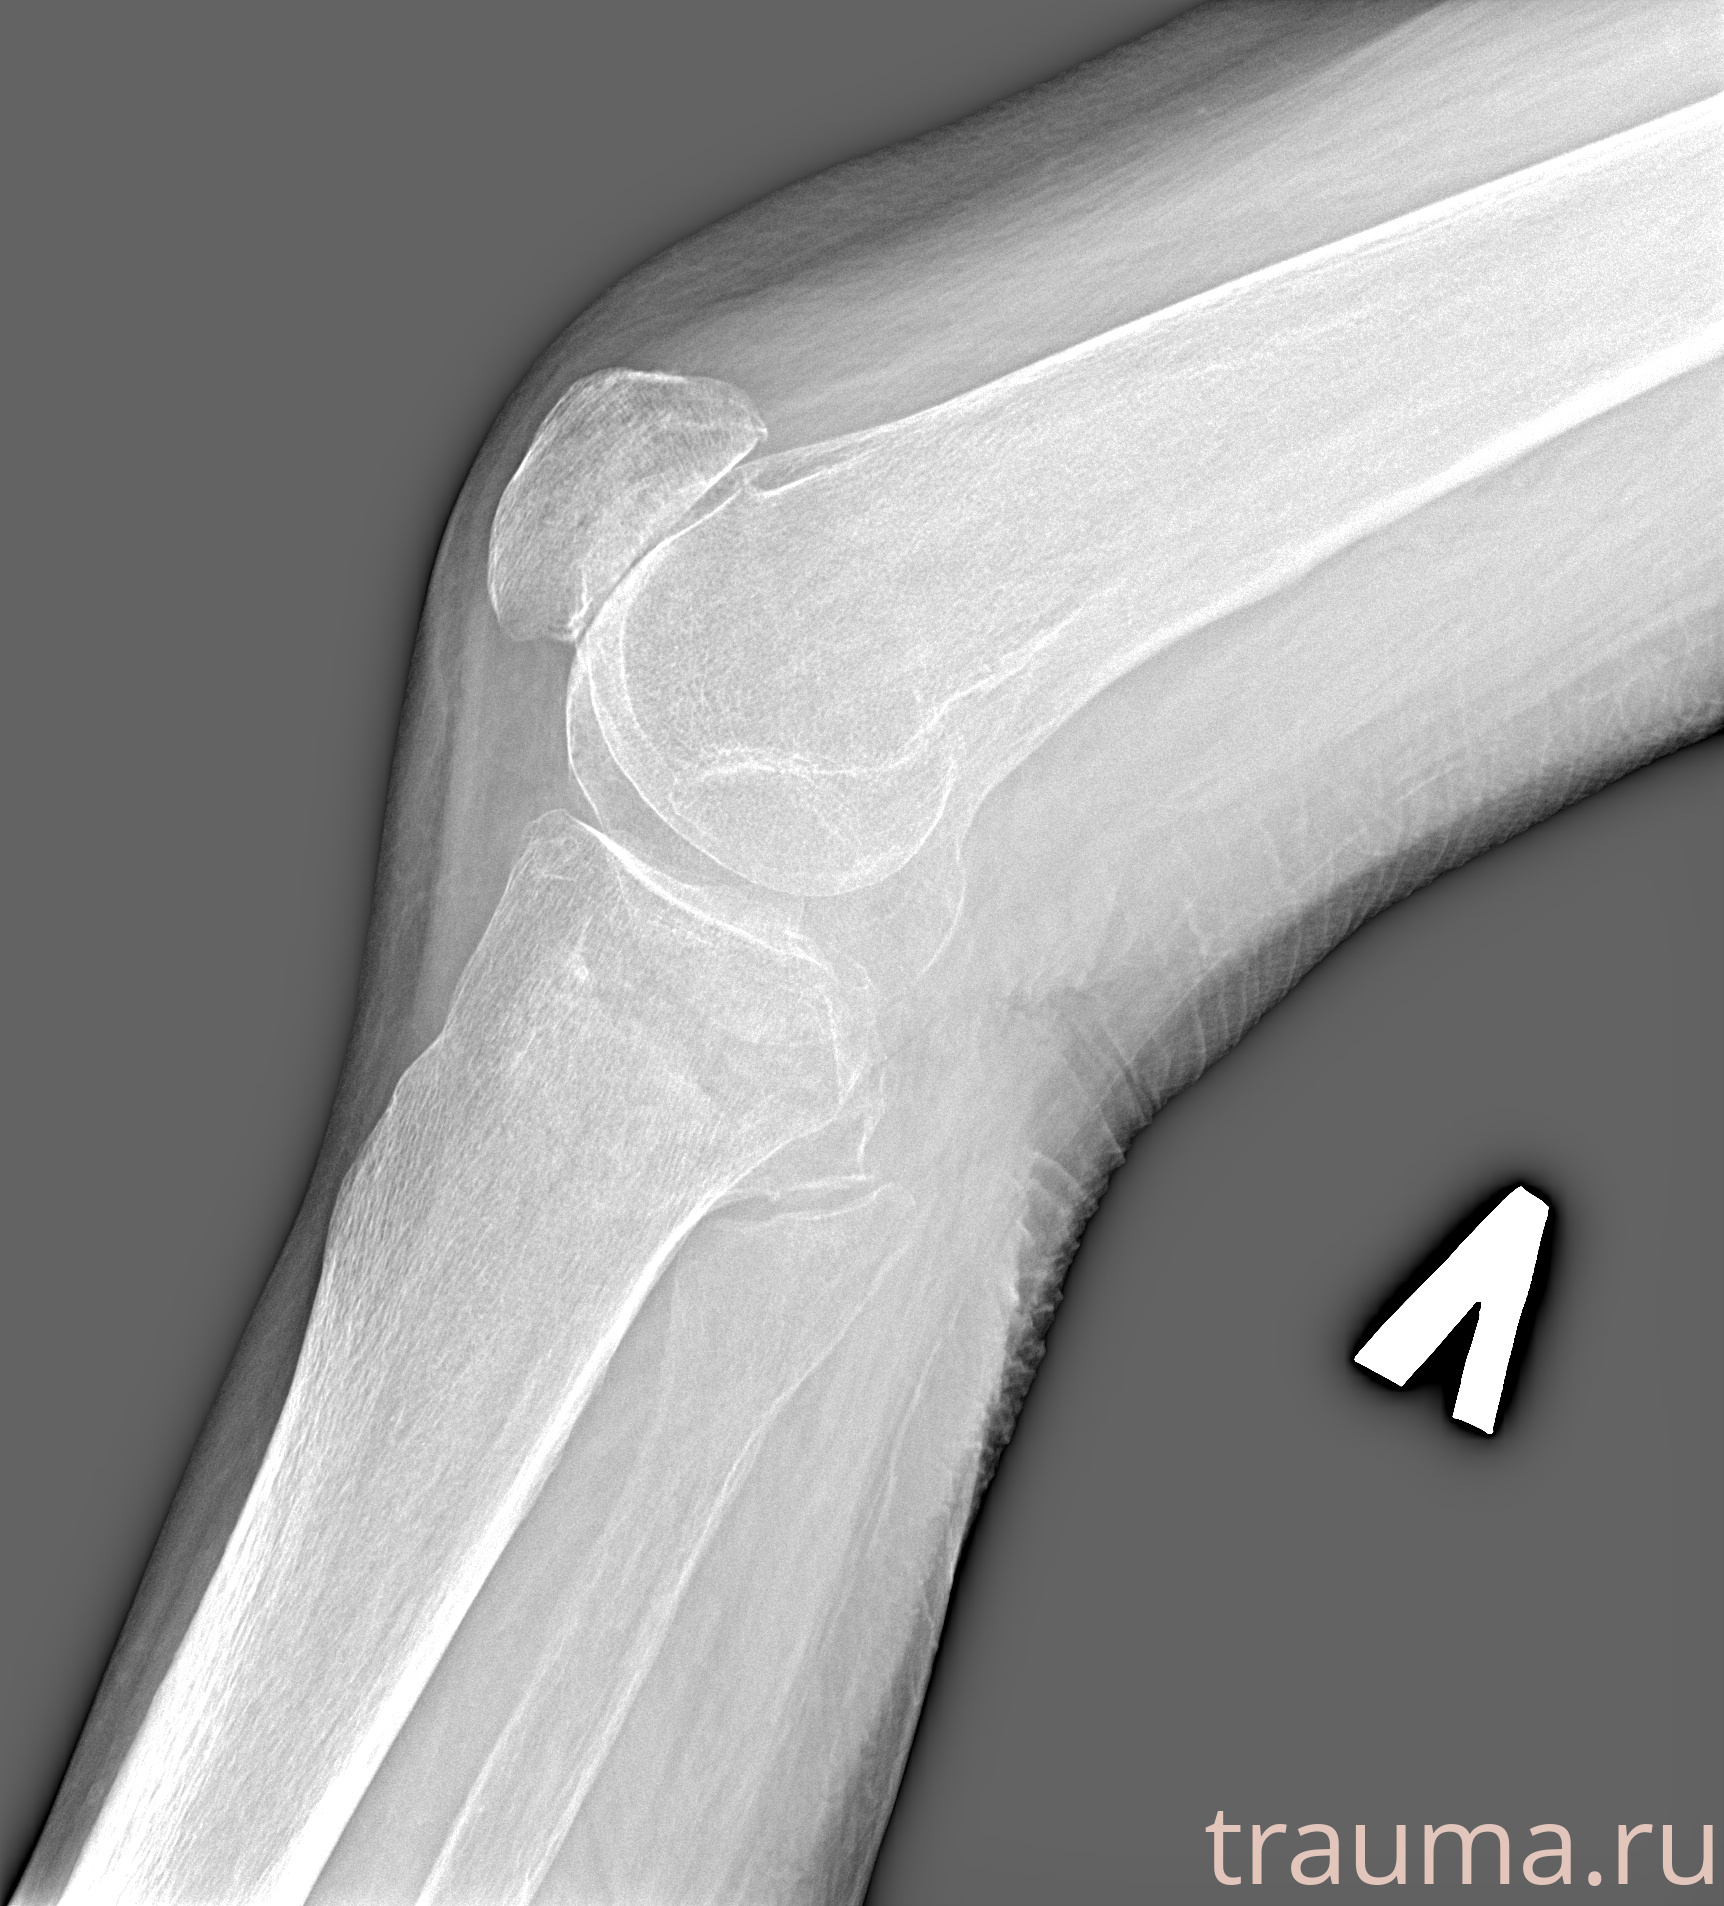

Рентгенограммы

Рентген на дому: по вашему адресу приезжает врач-рентгенолог, травматолог-ортопед с мобильным рентгеновским аппаратом, проводит диагностику травмы или заболевания, делает необходимые рентгенограммы, дает рекомендации по дальнейшему лечению. Получить качественные снимки в домашних условиях возможно благодаря уникальной методике, разработанной МосРентген Центром для института  Склифосовского